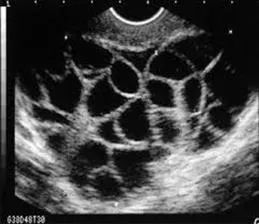

充满卵泡的卵巢

随之而来的潜在的风险就是OHSS。

患有OHSS的女性,可能会有不同程度的腹胀、恶心、呕吐、腹泻、体质量快速增加、少尿或无尿、血液浓缩、血容量不足、电解质紊乱、胸腔积液、心包积液、腹腔积液、呼吸窘迫综合征,伴血栓形成倾向的高凝状态及多器官功能衰竭。

而且,增大的卵巢如果发生卵巢扭转或卵巢囊肿破裂、出血等并发症,必要时也要采取手术治疗,有可能影响女性的生育功能。